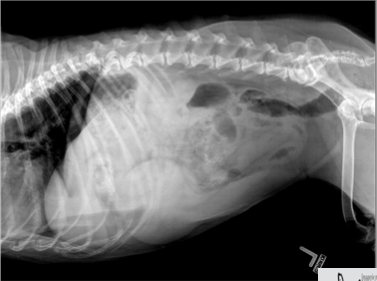

Quel est votre diagnostic radiographique?

Obstruction mécanique secondaire à un CÉ